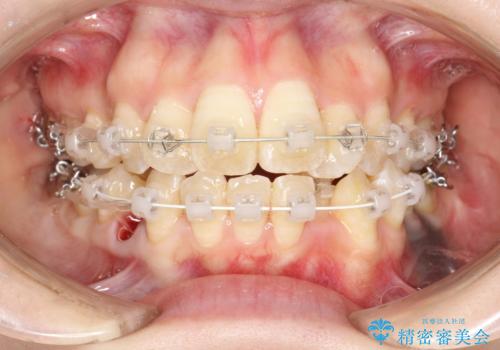

重度のガタガタ ワイヤーによる抜歯矯正

上下の歯に重度のガタガタがあり、前歯が下の歯と咬んでいない状態でした。

審美装置を用いた、抜歯矯正を行うこととしました。

抜歯したスペースを使うことで、ガタガタと出っ歯を改善することができました。